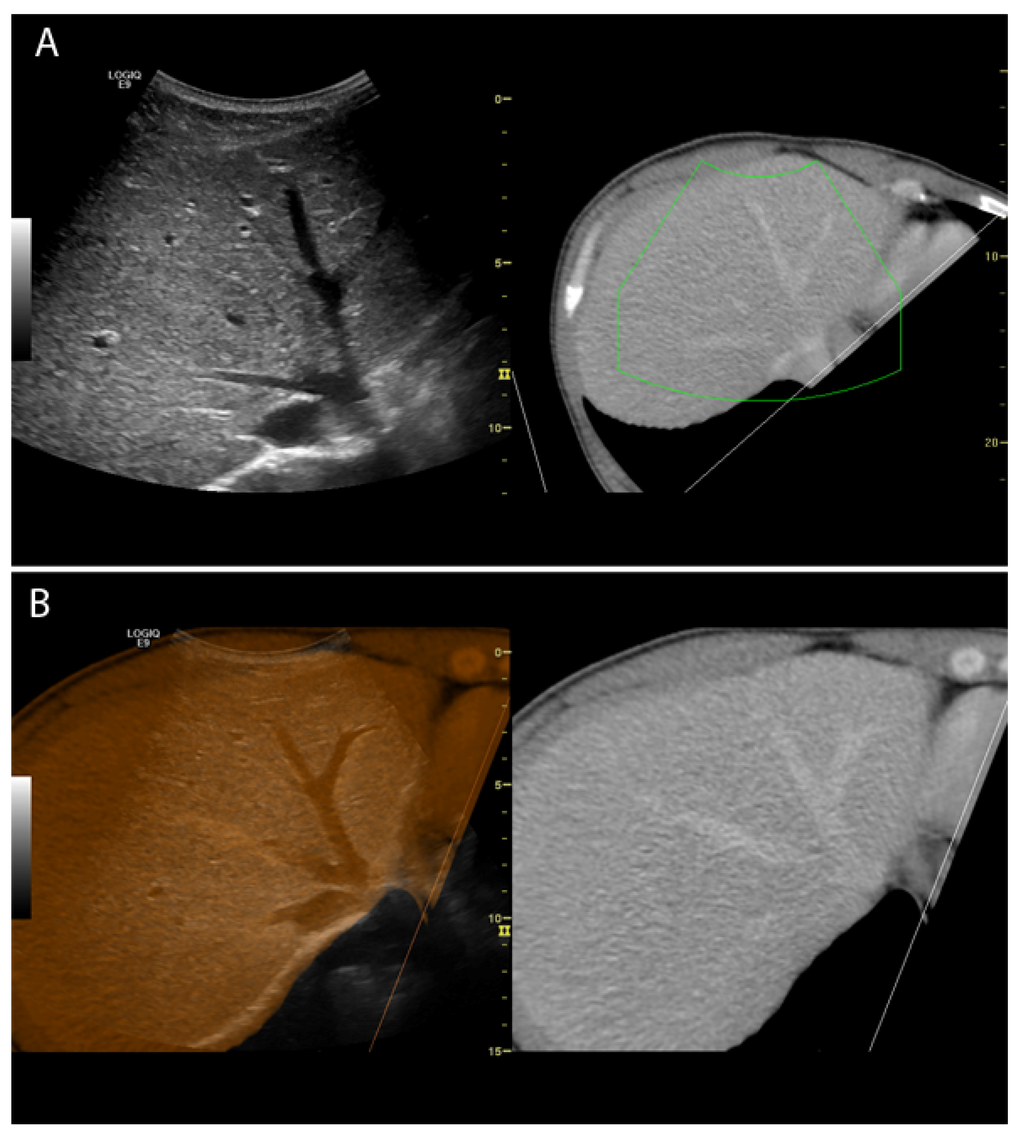

Figure 1.

(A) Co-registered images of the liver shown side by side (ultrasound (US): left; computed tomography (CT): right); The green box indicates the scanning area (B) CT and US images of the liver overlaid (left) and corresponding CT-image (right).

Image fusion involving real-time ultrasonography (US) is a method, where previously recorded computed tomography (CT) or magnetic resonance images (MRI) are shown simultaneously with live US images, hereby enabling one to benefit from two imaging modalities in one examination. The images can be shown side by side or in one single image where the images are overlaid/fused (Figure 1). After an initial co-registration the CT or MRI images are reformatted in a projection to fit the live US images. Image fusion is based on software and a magnetic positioning system, and is implemented into several commercially available US systems (GE, Hitachi, Esaote, Philips). Obvious advantages in image fusion are the possibility of real-time guidance on lesions that are difficult to distinguish sonographically, and improving overview in areas with limited US visualization; this could be of abscesses containing air, lesions in the hepatic dome or lesions hidden behind ribs [1,2,3,4].